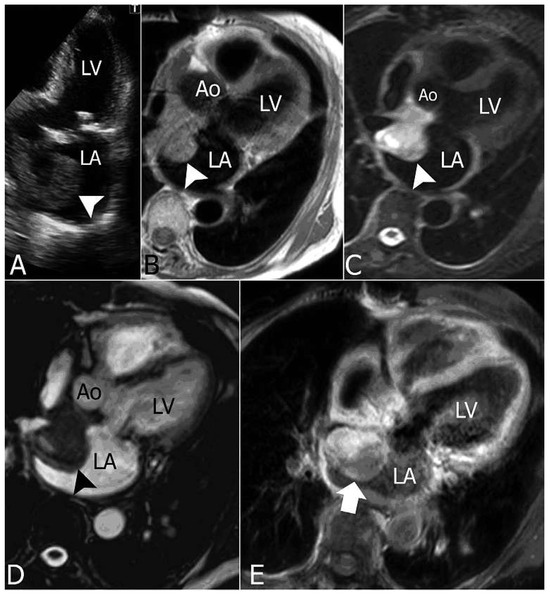

Primary Left Atrial Angiosarcoma Determining Severe Mitral Valve Stenosis

by Natalia Pavone, Vasileios Tsiopoulos, Riccardo Marano, Mariangela Novello and Mario Gaudino

Cardiovasc. Med. 2012, 15(2), 55; https://doi.org/10.4414/cvm.2012.01642 - 22 Feb 2012

Primary cardiac tumours are a rare pathogical entity. In the vast majority of cases these tumours are benign [1,2]; among malignant histotypes, angiosarcoma is the most common, representing 15–35% of all cardiac tumours [2,3]. Primary cardiac angiosarcomas usually arise from the right atrium [...] Read more.

Primary cardiac tumours are a rare pathogical entity. In the vast majority of cases these tumours are benign [1,2]; among malignant histotypes, angiosarcoma is the most common, representing 15–35% of all cardiac tumours [2,3]. Primary cardiac angiosarcomas usually arise from the right atrium or the pericardium; they typically occur in the third to fifth decade of life and are two to three times more frequent in males. We report a case of primary angiosarcoma arising from the left atrium in a female patient who had already undergone mitral valve repair. Full article

Show Figures

Figure 1